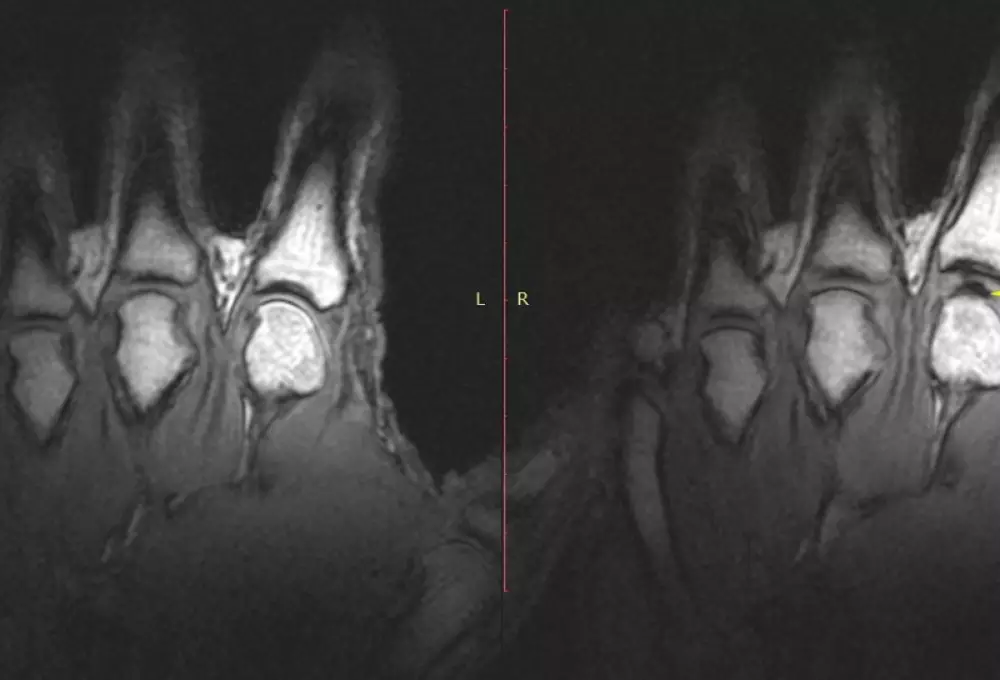

Медики раскрыли тайну хруста суставов Ученые наблюдали за хрустящими пальцами с помощью томографа. © Gregory Kawchuk

Чтобы поставить точку в этом вопросе, канадский специалист Грег Кочук (Greg Kawchuk) и его коллеги провели тщательное исследование "чемпиона по хрусту пальцев" Джерома Фрайера. Помощником ученых выступил современный томограф, способный получать информацию с большим временным разрешением.

Пальцы мужчины помещались в специальные трубки, которые осторожно вытягивали их, пока тот неподвижно лежал в томографе, - и тем самым заставляли хрустеть. Весь процесс разворачивался около 300 миллисекунд и впервые предстал изумленным глазам ученых во всех деталях.